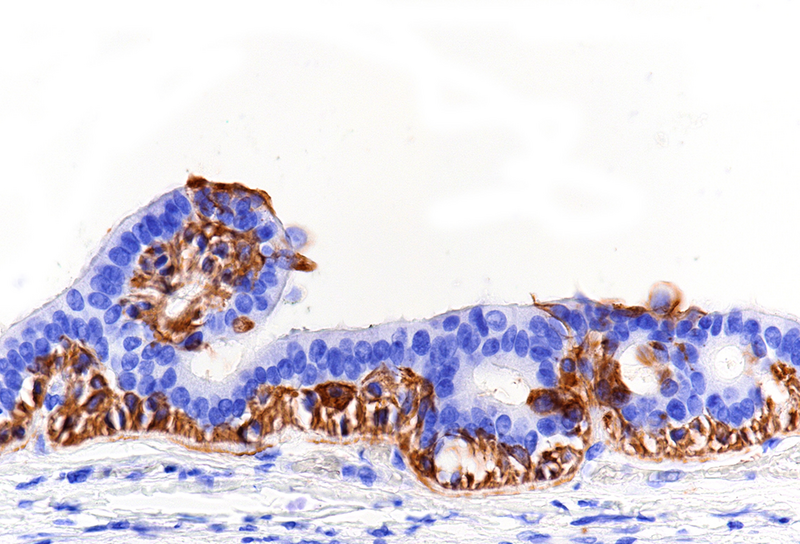

Histological examination disclosed a hybrid cyst lining epithelium, composed of a luminal layer of columnar cells with slightly basophilic cytoplasm and signs of mucin production, while slightly darker cuboidal cells without specific differentiation were present basally (Panel B-C). The cells exhibited mild nuclear irregularities, but no true dysplastic or malignant features were observed. The fibrotic cyst wall contained no skin adnexal structures, neural tissue, smooth muscle bundles or specific stroma. Immunohistochemical studies showed strong and diffuse reactivity for cytokeratin 7 of both epithelial layers (Panel D). In addition, the basal epithelial cell layer demonstrated immunoreactivity for cytokeratin 5/6 (Panel E) and p40 (Panel F). No immunohistochemical reactivity was observed for CDX2, CK20, PAX8, estrogen and progesterone receptors. Based on the morphological and immunohistochemical features, the diagnosis of a benign cyst lined by anal gland epithelium (“anal gland/duct cyst”) was made.